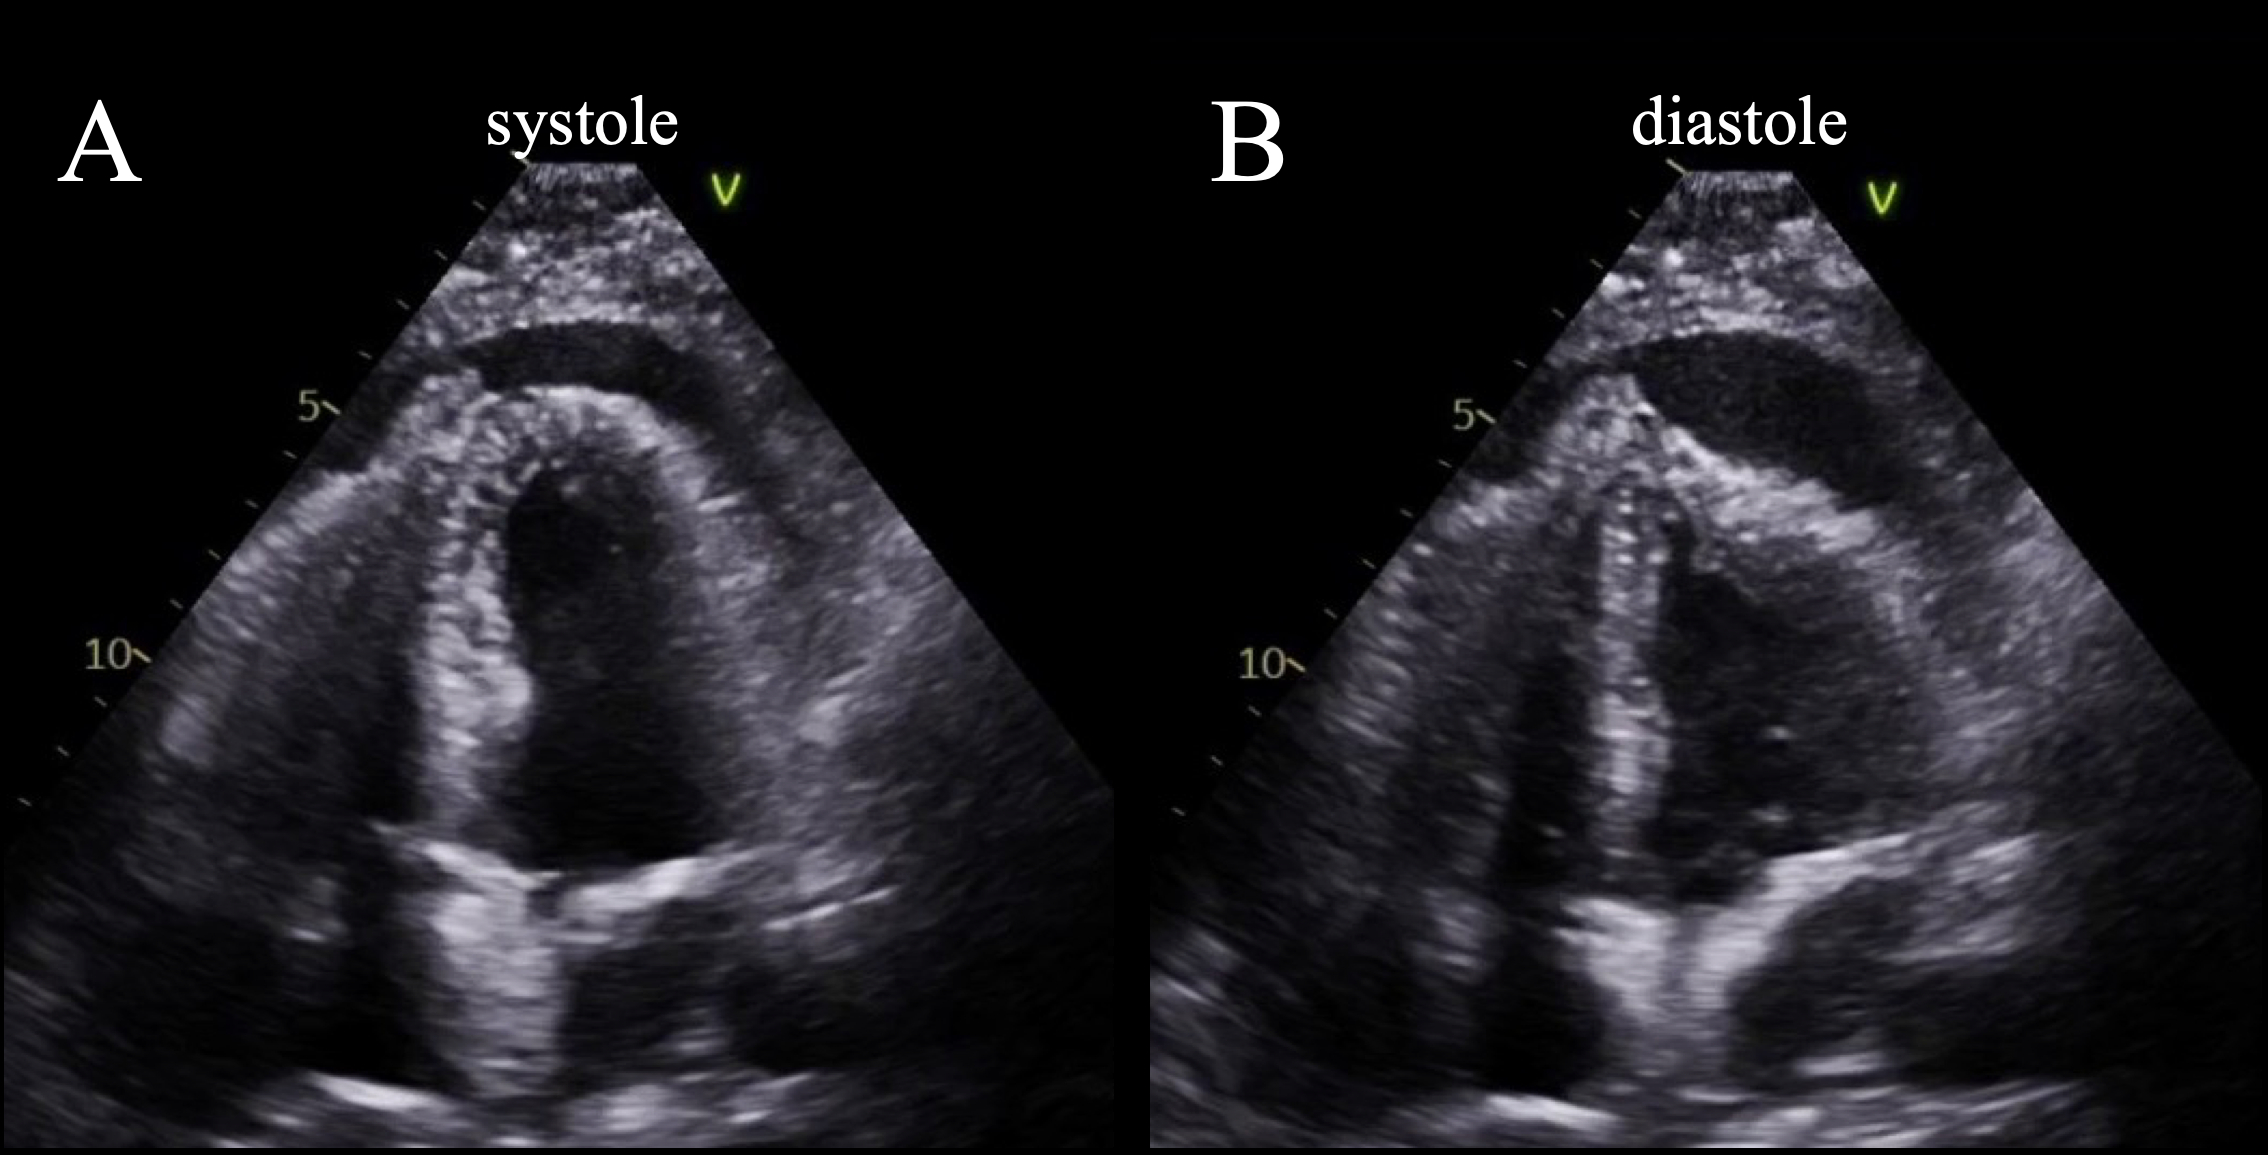

A 63-year-old man with metastatic EGFR-positive non–small-cell lung cancer and recent pulmonary embolism on rivaroxaban was admitted following elective pleural-peritoneal shunt placement for recurrent malignant pleural effusions. Transthoracic echocardiography (TTE) was notable for a small pericardial effusion on post-operative day 1. On post-operative day 2, he developed hypotension (BP 86/56 mmHg), tachycardia (HR 115 bpm), and elevated lactate (2.9 mmol/L; normal range 0.5 – 2.0 mmol/L). Exam revealed distant heart sounds and jugular venous distension. Repeat TTE demonstrated a large, loculated pericardial effusion with diastolic collapse of the lateral and apical LV (Figure 1), right ventricle, and atria, along with respirophasic mitral/tricuspid inflow variation and expiratory hepatic vein flow reversal. Emergent subxiphoid surgical pericardial window revealed dense adhesions and evacuated 500cc bloody effusion, with immediate hemodynamic improvement. Histopathology confirmed malignant pericardial involvement with clusters of malignant adenocarcinoma cells (Figure 2).

Here we highlight a visually compelling example of tamponade with LV diastolic collapse secondary to a loculated malignant pericardial effusion. LV diastolic collapse is a hallmark sign of regional cardiac tamponade, especially in malignancy or postsurgical states. Prior studies utilizing canine models of regional cardiac tamponade demonstrated that LV diastolic collapse correlated with significant reductions in cardiac output and mean arterial pressure prior to decompensated tamponade. Early recognition of regional tamponade and hallmark signs including LV diastolic collapse is critical to guide interventions and avoid hemodynamic deterioration.